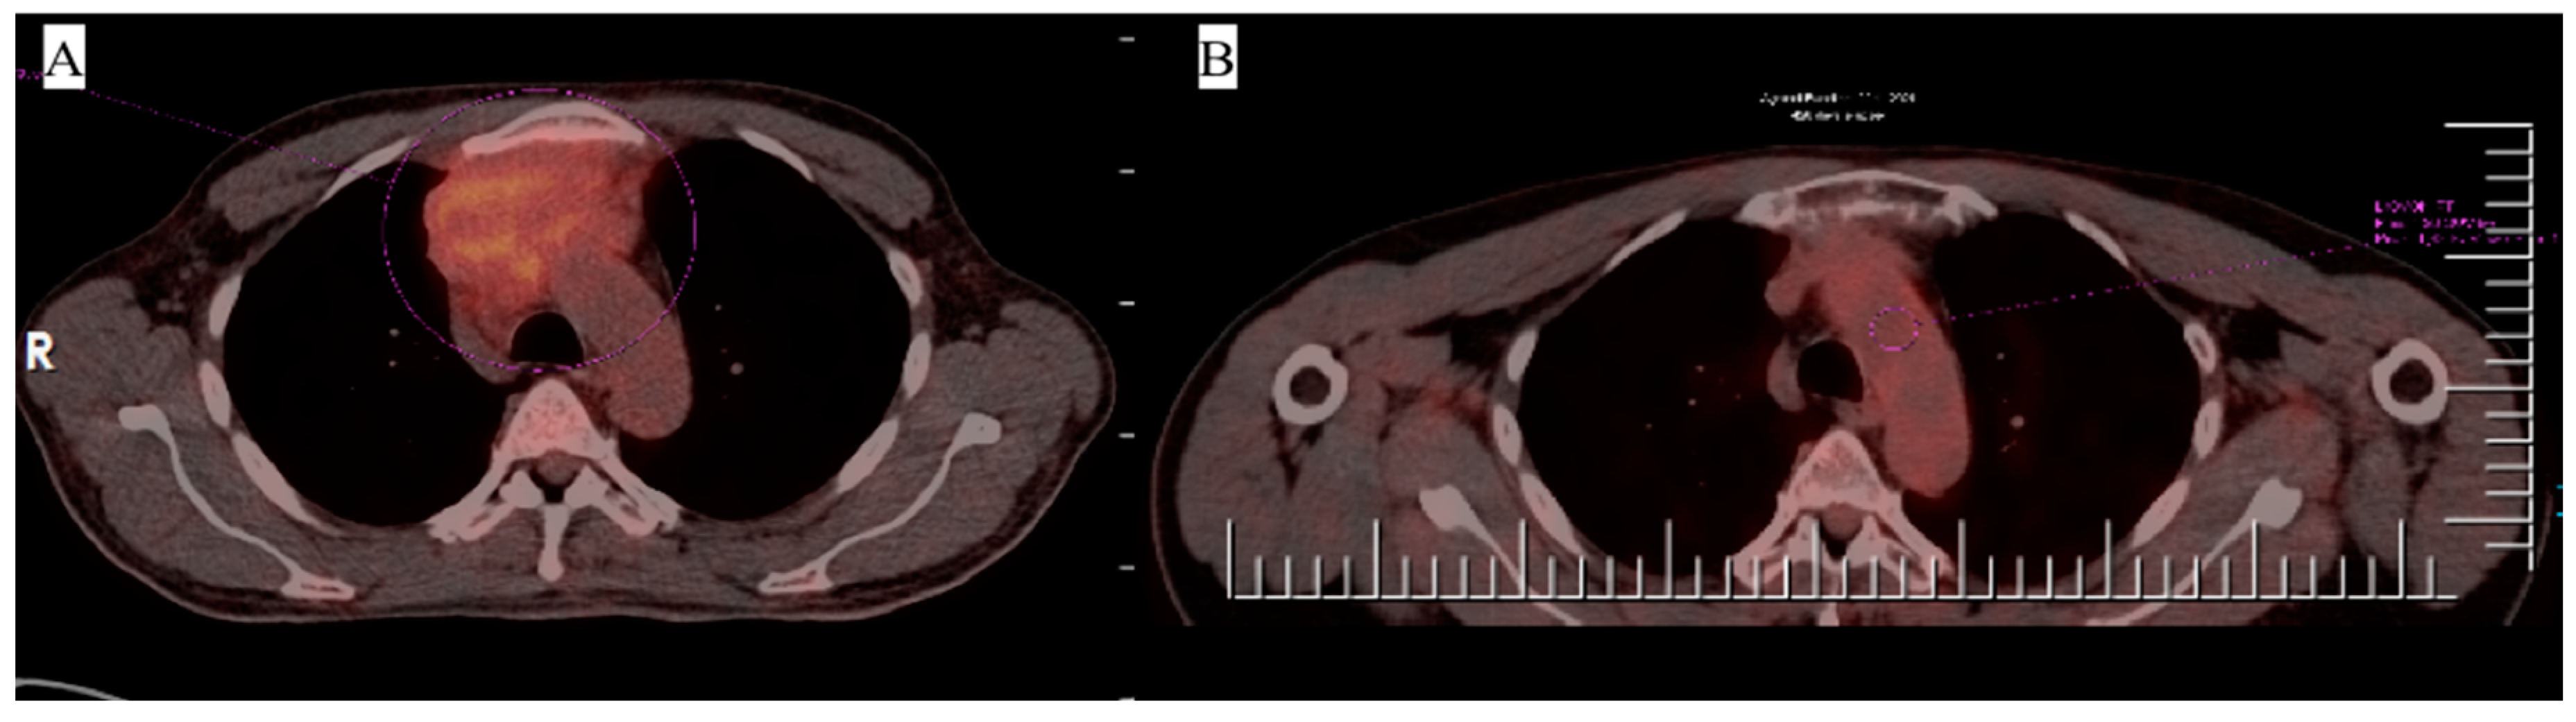

3. Case 1

4. Case 2